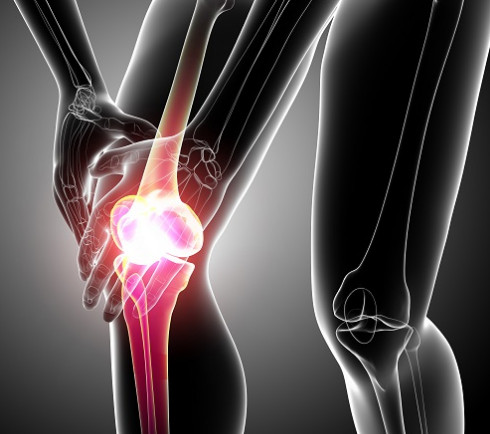

퇴행성 관절염 말기증상

퇴행성 관절염 말기에는 관절의 강직이 생겨 무릎이 다 펴지지 않거나 무릎을 구부릴 때 제한이 생길 수 있고 걸을 때 통증이 매우 심해지고 다리를 움직이지 않는 밤에도 통증이 심해 잠을 설치는 경우도 있습니다. 연골이 완전히 닳아 없어진 말기에는 인공관절수술을 해야 하는데, 인공관절수술은 말 그대로 인공으로 만든 관절을 끼워 넣는 수술로 손상된 연골 부분을 제거하고 그 위에 인공 관절을 삽입하는 수술입니다.